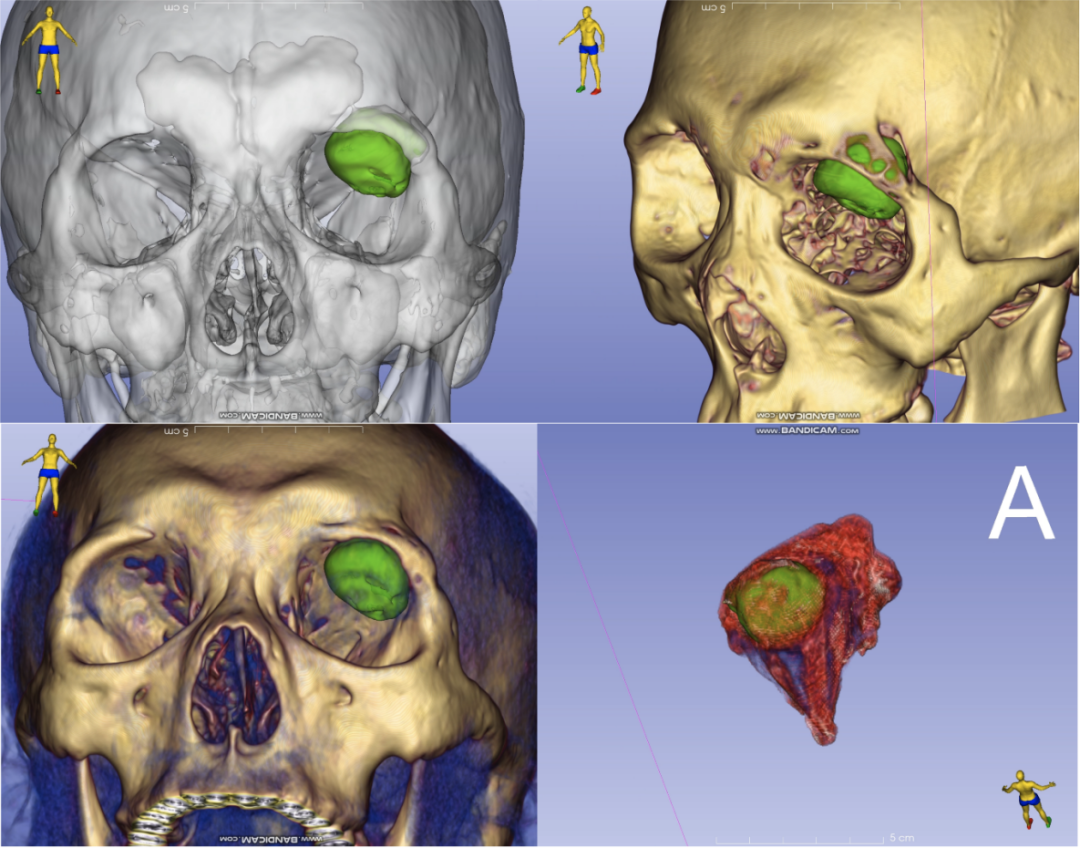

如何在彻底切除肿瘤的同时,兼顾患者容貌恢复与快速康复需求?陶钧教授与孙一洲副教授反复研读影像资料,结合病变三维重建图像,从不同角度反复比较眼科手术入路及神经外科手术入路的优缺点,最终一致认为采用眼科入路联合神经外科应用显微镜的方案创伤小且安全,从而最终敲定创新手术方案:由眼科经眉弓外侧入路,在不移除眶壁的前提下从眶内暴露肿瘤,该路径切口沿眉毛弧度设计,隐蔽且美观、不损伤眶壁、创伤小;再由神经外科借助显微镜进行肿瘤精准切除,凭借成熟的颅底显微操作技术,在显微镜下高倍放大肿瘤,在1mm级的缝隙内锐性分离肿瘤与硬脑膜及眶周筋膜的界面,从而将并发症风险降至最低。

患者三维重建图像,绿色示肿物